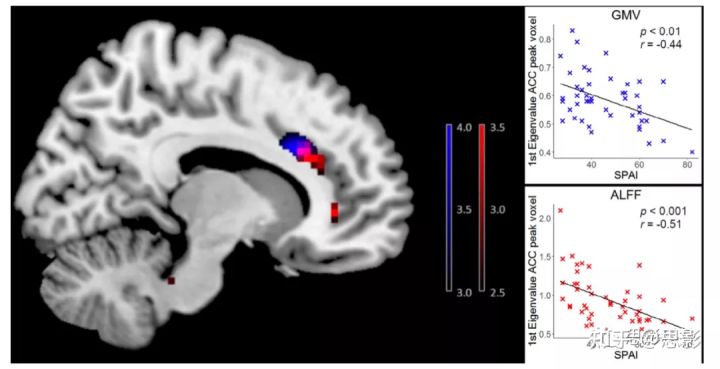

图2 GMV、ALFF在前扣带和行为评分的相关分析所有被试的扣带皮层SPAI(智能手机成瘾量表)与GMV(蓝色)和ALFF(红色)分别呈负相关。把年龄、性别作为协变量,全脑回归分析结果显示与TIV (VBM)或FD (ALFF)相关,未校正,k > 80 (VBM)和k > 5体素(ALFF) ,p < 0.001。颜色条表示t值。图中显示了SPAI总得分与GMV或ALFF参数估计之间的关系(峰值体素提取的GMV值和ALFF值)。

回归分析显示,在包括中扣带皮层和ACC的团块中,SPAI得分与GMV呈负相关(x = 12, y = 21, z = 29, z = 3.91, k = 187);如图2所示。SPAI与GMV在左眶后回(OFC, x = 33, y= 29, z =−11,z = 3.99, k = 146)和右枕下回(x = 44, y=−75,z = 9, z = 3.91, k = 138)均呈负相关。

回归分析显示,SPAI与右侧ACC (x = 9, y = 27, z = 27, z = 3.88, k = 9)和双侧中央前回(左:x =−48,y = 6, z = 27, z = 3.62, k = 6;右:x = 42, y = 0, z = 36, z = 4.07, k = 5)的ALFF值呈负相关;参见图2。此外,SPAI评分与右侧梭状回(x = 33, y =−21,z =−30,z = 4.33, k = 23)等团块的ALFF呈正相关。

第三,SPAI评分与GMV和ALFF的关联都集中在ACC上。

本研究的第二个重要发现是,与对照组相比,SPA患者的ACC(前扣带回)活性较低。此外,SPAI评分与GMV和ALFF之间的关联都集中在ACC上。ACC被认为是奖赏系统的一部分,与渴望和抑制控制相关,在没有接触药物刺激的物质使用障碍个体中表现出较低的活性;而ACC激活被认为与线索诱发的渴望相关。值得注意的是,在IGD的研究中也发现了ACC GMV的降低,且ACC的GMV与受影响个体的认知控制表现和冲动性呈负相关。Yao及其同事的一项系统综述和meta分析强调了IGD中ACC的结构和功能改变。此外,最近的一项研究为使用微信成瘾提供了进一步的ACC体积减少的证据。在目前的多模态研究中,我们观察到ACC对SPA的结构和功能方面的贡献。与其他研究的结果一致,这项研究的结果清楚地表明,ACC改变不是SPA(或任何其他行为成瘾)所特有的。相反,考虑到ACC与人类行为的多个维度和心理过程的相关性,这个大脑区域的神经完整性的改变更反映了跨疾病的神经特征。